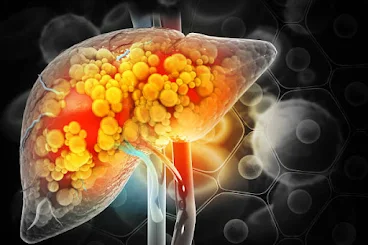

Fatty liver disease, also known as hepatic steatosis, occurs when fat builds up in the liver. This condition can lead to liver inflammation and damage if not managed properly. Understanding the symptoms, treatment options, causes, and recommended diet is crucial for those affected by or at risk of fatty liver disease.

Fatty liver disease occurs when more than 5% to 10% of your liver's weight is fat. It is classified into two main types: